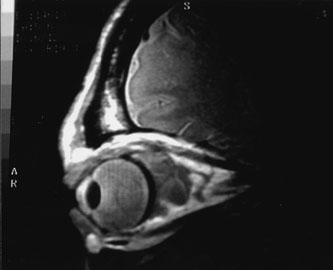

Investigations

Contrast-enhanced CT of the orbits with direct and coronal cuts is the radiologic study of choice for these patients.45 A well-demarcated, encapsulated oval or rounded mass is revealed, which is typically intraconal in the lateral part of the middle third of the orbit (Fig. 5) but occasionally may extend to the extraconal space.42 Septa within the tumor may be apparent on high-resolution CT. The posterior pole of the globe frequently is indented by the rounded anterior margin of the tumor.42 The optic nerve typically is displaced rather than surrounded by the tumor. Subtle outward bowing of the lateral orbital wall or increase in orbital size may be present, consistent with a long-standing, slowly growing mass lesion.10,42 Enhancement with intravenous contrast occurs and may be homogeneous or inhomogeneous.10,45 Rarely, cavernous hemangiomas may occur as an intraosseous tumor within the orbital or facial bones.42,53–55 Although usually an isolated intraorbital lesion, multiple lesions in one orbit occurred in 8 of 164 (5%) patients of three combined large studies,10,42,45 and bilateral multiple cavernous hemangiomas also have been described.56 In contrast to patients with venous flow malformations in which phleboliths are common, phleboliths are rare in cavernous hemangiomas. Three large studies comprising 164 patients with cavernous hemangioma all reported that no calcification was detected within the tumor.10,42,45If the diagnosis is still unclear or if better definition of details and localization of the lesion is required, then MRI should be performed. Magnetic resonance imaging demonstrates nonspecific characteristics of a lesion isointense to muscle and gray matter on T1-weighted images and hyperintense on T2-weighted images (Fig. 6).57 The lesions show initial central patchy enhancement, which fills up homogeneously within 20 to 60 minutes.58 If ultrasonography is performed, B-scan ultrasonography shows a well-circumscribed mass with a sharply defined anterior acoustic border.23 A-scan ultrasonography shows high reflectivity of the echo signals resulting from the multiple blood-filled vascular channels, regular internal structure with a higher anterior and posterior spike marking the capsule, and moderate sound attenuation (angle of decrease of the echo spike within the lesion).24 Arteriography is not indicated.

Fig. 6. Cavernous hemangioma. Axial magnetic resonance imaging demonstrates a well-defined, homogeneous intraconal mass that is isointense to muscle and gray matter on T1-weighted image (A), and hyperintense on T2-weighted image (B). Note the displacement of the optic nerve and indented posterior globe.